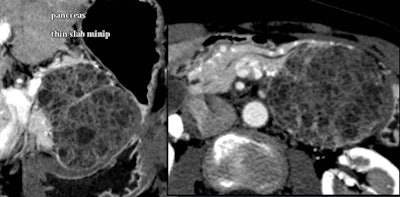

Small cystic lesions not worrisome for malignancy under 3 cm include side branch IPMNs, and serous microcystic adenomas, which are easily characterized by their honeycomb matrix that is also easily seen on ultrasound, Jeffrey said.

Serous cystic tumors are by far the most common pancreatic cystic lesions, Jeffrey said. They are nearly always microcystic, with macrocystic serous lesions occurring in about 4% of cases. They also are benign and can be managed with follow-up but not surgery, he said.

It's also worth noting that small cystic lesions are quite common, especially with advancing age. And the vast majority, including side branch IPMNs, microcytic adenomas, and epithelial cysts, are benign, Jeffrey said.